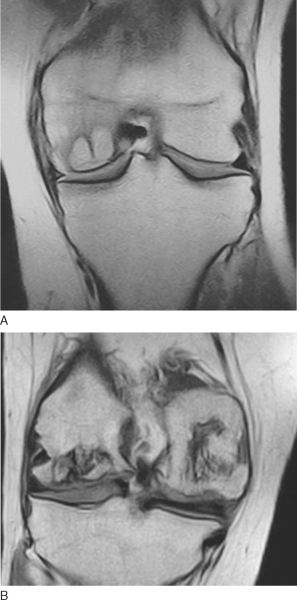

Magnetic resonance imaging can help confirm the diagnosis and the extent of the lesion (

Fig. 54-2

)

Figure 54-2 |